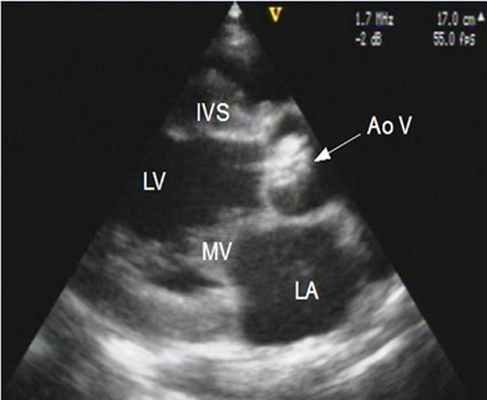

- ЭхоКГ. ЭХОКГ позволяет определить: структуру клапана (двустворчатый клапан, утолщение створок, фиброз, кальциноз, вегетации), характер его движения (подвижность створок, степень открытия) и площадь отверстия; изменения корня аорты (постстенотическая дилатация), объем левого желудочка, выраженность гипертрофии левого желудочка, нарушения локальной сократимости левого желудочка (указывающие на ИБС), ФВ, объем левого предсердия, состояние других клапанов. Доплеровское исследование позволяет с высокой точностью определить градиент давления между аортой и левым желудочком.

В диагностики порока применимы такие методы как рентгенграфия органов грудной клетки и эхокардиография (ЭхоКГ) . На рентгенограммах в первые два дня после рождения отмечается умеренная увеличение тени сердца, в ряде случаев диагностируется картина интерстициального отека легких. Метод ЭхоКГ позволяет: - определить локализацию и характер обструкции выводного отдела левого желудочка; выявить морфологические особенности аортального клапана; оценить степень выраженности стеноза; измерить диаметр фиброзного кольца клапана аорты; оценить функциональное состояние левого желудочка; обнаружить другие сопутствующие ВПС. Наиболее важным в принятии решения вопроса о сроках выполнения операции — градиент систолического давления на клапане аорты, который также определяется по данным ЭхоКГ.

4. Эхокардиография (УЗИ-сердца) - является основным методом диагностики и оценки прогноза больных с аортальным стенозом. При этом возможна визуализация структур корня аорты и выносящего тракта левого желудочка, оценка подвижности створок и их состояния, определение локализации стеноза.